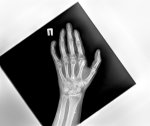

>>1608863

Алсо, если у тебя боли в коленях, типа воспаления, то попробуй жрать чеснок и куркумин с перцем.

Аноним 19/03/25 Срд 15:01:53 #31 №1608936